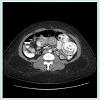

Abdominal series revealed small bowel obstruction with multiple air-fluid levels. Computed axial tomogram of the abdomen confirmed small bowel obstruction with proximal dilation of the small intestine and a mottled intraluminal mass in the Roux limb (Figure 1 and 2).

Abdominal series revealed small bowel obstruction with multiple air-fluid levels. Computed axial tomogram of the abdomen confirmed small bowel obstruction with proximal dilation of the small intestine and a mottled intraluminal mass in the Roux limb (Figure 3 and 4). Following fluid and electrolytes resuscitation, patient underwent diagnostic laparoscopy, enterotomy of the common channel and removal of the ball of hair within the lumen of the jejunojejunal anastomosis (The operative procedure was similar to the case described above). The enterotomy was repaired in two layers using absorbable sutures. Postoperative recovery was unremarkable.

The advert of multi-slide computed axial tomogram has herald a new era of diagnostic capability for small bowel bezoars as it has significantly improved preoperative diagnosis. Currently, abdominal CT scan is the diagnostic modality of choice for detecting small bowel bezoars as it can also detect additional bezoars within the gastrointestinal tract. Traditionally, oral contrast is administered during such study. Care should be taken to ensure that the patient does not aspirate the contrast. Characteristic radiologic findings consist of intraluminal mass with a mottled appearance due to the presence of air within the interstices [15]. These findings may mimic small bowel fecalization or many other clinical entities such as intraluminal tumors. CT findings in conjunction with findings on exploration namely hard junks of particulate matter often near the ileocecal valve should be considered pathognomonic for small bowel bezoars. It warrants a mandatory search for the site of the bezoar, which can include an intra-operative Endoscopy to exclude gastric bezoar showering to the small bowel.